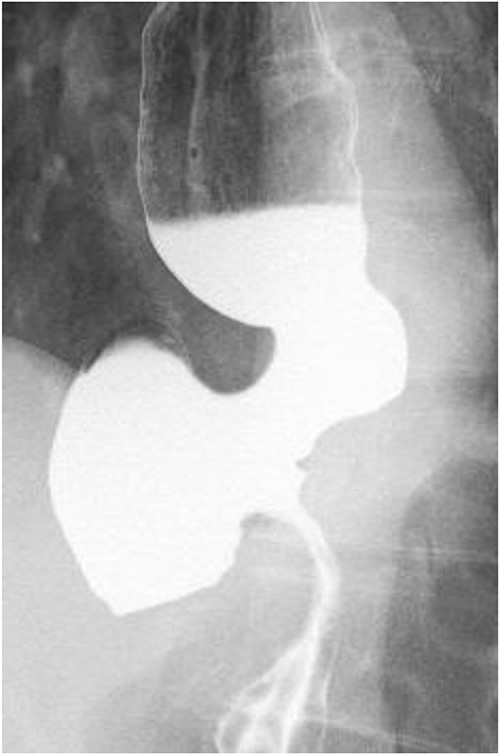

A 60-year-old female with dysphagia and vomiting visited the university hospital. In 2007, she underwent esophageal diverticulum resection (procedure unknown) with a diagnosis of an esophageal diverticulum, which subsequently recurred. In 2011, she underwent a transesophageal hiatus diverticulectomy and a fundoplication (Nissen procedure) at a local hospital. In 2013, dysphagia and vomiting appeared. The patient was diagnosed with recurrence and underwent balloon dilatation for follow-up. In 2015, the patient came to our hospital due to persistent symptoms. After one balloon dilation, the patient did not show any improvement and was referred for surgery. Esophageal fluoroscopy revealed a diverticulum 5 cm in size in the lower esophagus just above the eruption. There was no significant change in the diverticulum size before and after dilation (Figs 1 and 2). Gastrointestinal endoscopy revealed a diverticulum in the lower esophagus, with a residue accumulation (Fig. 3). The esophagus directly below the diverticulum was narrowed. The patient was diagnosed with recurrent lower esophageal diverticulum and underwent surgery.

Esophageal fluoroscopy (before dilation). There was a 5 cm-sized diverticulum in the lower esophagus just above the eruption.